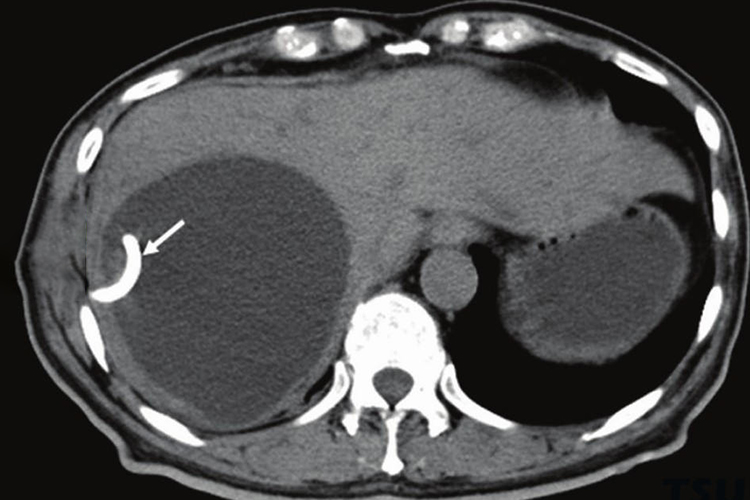

典型的肝囊肿CT图显示为圆形或卵圆形,外壁与周围正常肝组织界线分明。肝囊肿可单发或多发,有时形态不规则,伴有出血时,可出现漂浮的弥散性点状低回声,囊壁可增厚,边缘不规则。

肝囊肿的治疗应视其大小、性质及有无并发症而定。直径5cm并出现压迫症状者,可在超声引导下穿刺抽液,以缓解压迫症状。囊肿有感染时,宜行外引流术。当有并发症出现如囊肿破裂、囊蒂扭转、囊内出血或囊肿巨大,压迫邻近器官,影响进食者,需外科手术治疗。